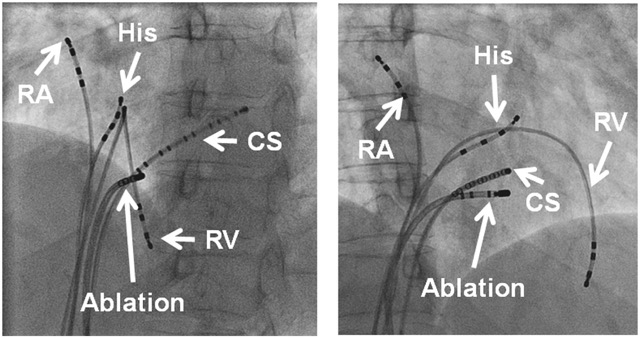

3. Catheter ablation for SVT – Ablation involves a procedure where fine wires are advanced from veins at the top of the leg to the heart. Pacing the heart can then induce SVT. Heat applied from the tip of one of the wires causes a tiny area of localized tissue damage (the tissue is cauterized, or more properly ‘ablated’). This destroys one limb of the abnormal circuit and so cures the arrhythmia. The abnormal limb in AVRT is the accessory pathway, in AVNRT it is the AV nodal slow pathway and in atrial tachycardia the focal spot it is arising from is the abnormality or part of a reentry circuit.

Ablation of SVT has very high success rates – >95% chance of a permanent cure with one procedure, and ablation can be repeated if necessary if it recurs.

Oliver Segal SVT treatment AVNRT.jpeg